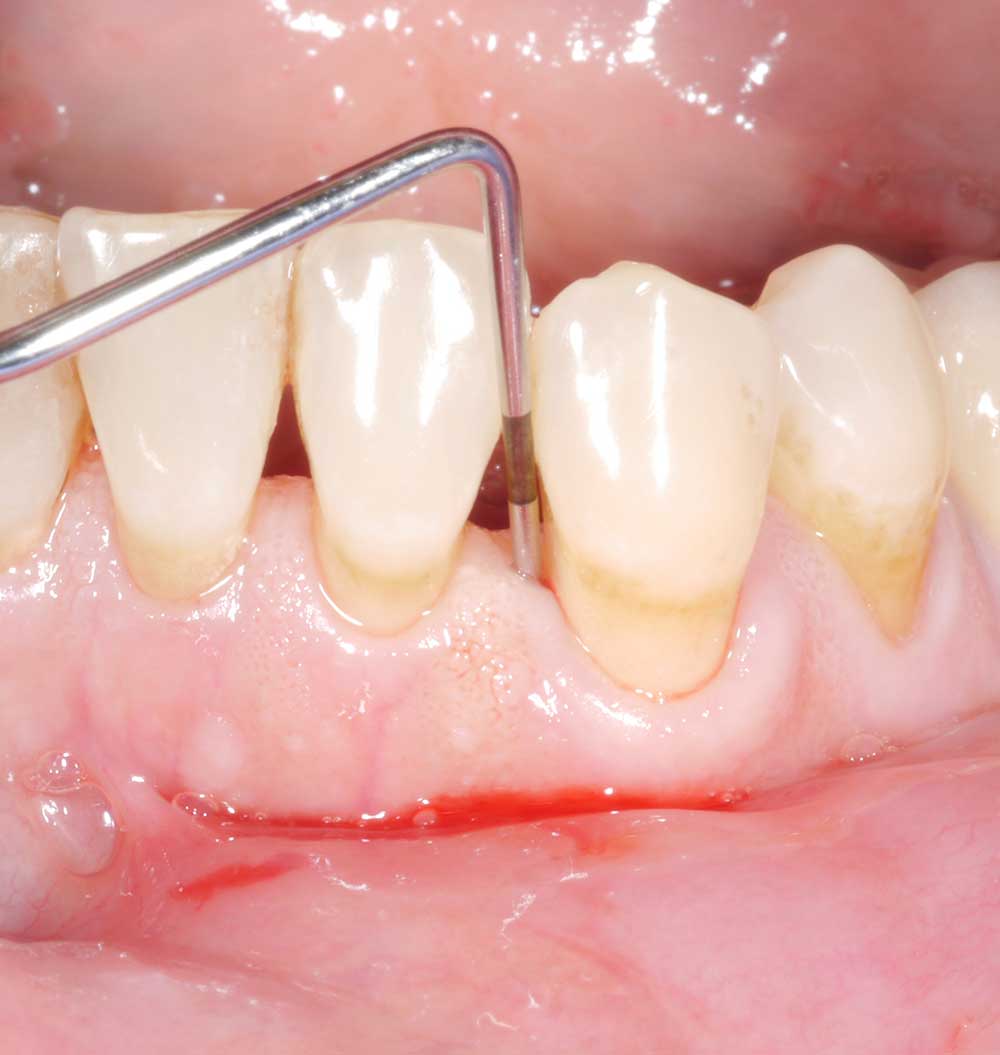

Regarding the second question: either type of probe can be used – metal or plastic. However, depending on the type of prosthetic restoration, the plastic probe may have certain advantages. In certain cases (e.g. patients with overhanging crown designs or implant-retained complete dentures), the slight flexibility of the plastic probe provides better access and therefore probably more accurate measurements. The Figure shows just such a case, of a patient with an implant-retained complete denture (a). Figures (b) and (c) show that probing depth differs substantially depending on the type of probe used. Whereas probing with the metal probe yielded a depth of 3 mm (b), the measurement for the plastic probe was substantially higher (c) – 8 mm! After removal of the prosthetic restoration (Figures [d] and [e]), the probing depths are the same for both types of probe – approx. 10 mm. Depending on the access and the patient’s prosthetic restoration, thought should be given in the dental practice as to whether the slight flexibility of a plastic probe might provide better access and thus more accurate measurements.

Regarding the third question: measurements around implants with and without prosthetic restorations often differ from each other by at least 1–2 mm (Serino et al., 2013). To ensure exact measurements are taken, it is therefore recommended to remove the restorations of patients who are suspected of having peri-implantitis (see article ‘How to correctly diagnose peri-implantitis’) – providing the restoration is screw-retained/removable. However, this is not recommended as standard routine and/or for patients with a healthy peri-implant status.